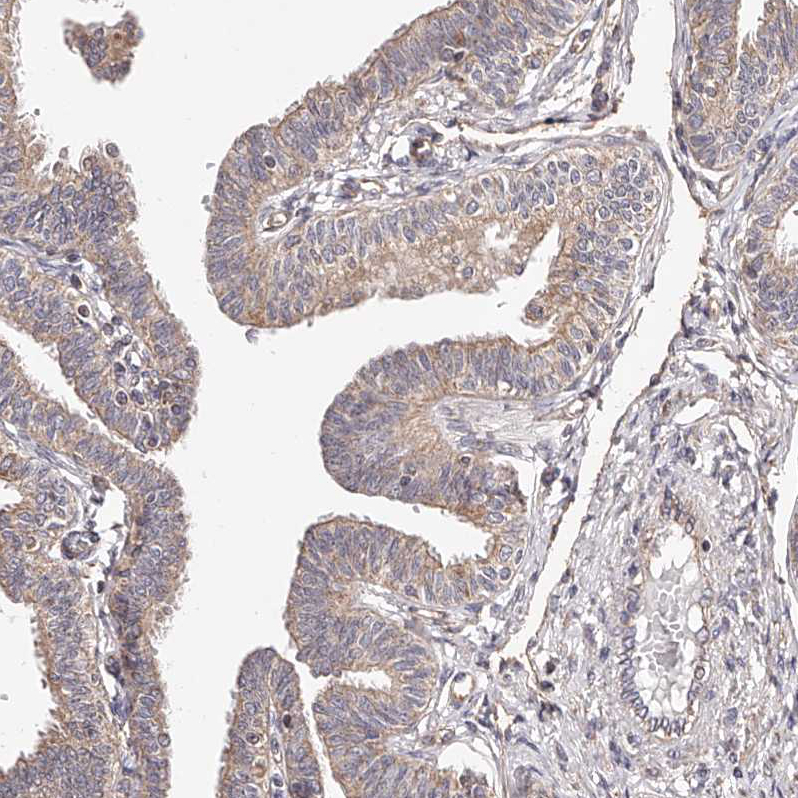

Immunohistochemical staining of human fallopian tube shows moderate cytoplasmic positivity in glandular cells.